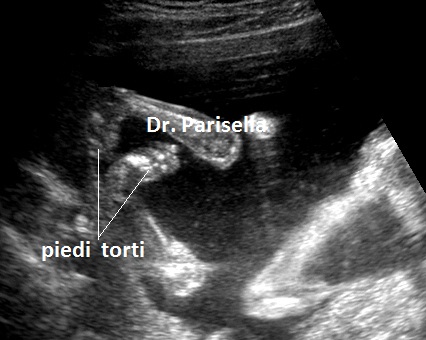

Il quadro malformativo conseguente alla sequenza ipo-acinesia-deformazione-fetale è legato ad una sequela di eventi caratteristici: a livello degli arti inferiori i gruppi muscolari più potenti sono gli estensori per cui gli arti inferiori saranno estesi e i piedi torti avranno un atteggiamento equino-varo; agli arti superiori prevalgono i muscoli flessori per cui le braccia saranno flesse davanti al torace, mani chiuse a pugno e in deviazione ulnare con clinodattilia; la paralisi del diaframma e dei muscoli respiratori sarà responsabile dell'ipoplasia toracica e polmonare; il blocco dell'articolazione temporo-mandibolare determina micrognazia; il blocco dei muscoli orbicolari determina microstomia. Ovviamente l'evento funzionale più evidente all'esame ecografico sarà rappresentato dall'assenza di movimenti attivi fetali.

4) anomalo atteggamento di mani e piedi: mano in deviazione ulnare, clinodattilia, piede torto equino-varo